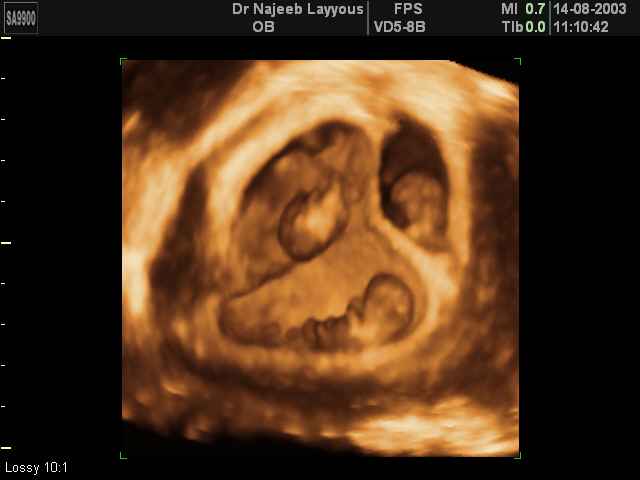

- صور لتوائم

صور لتوائم بجهاز الالتراساوند ثلاثي الأبعاد | الدكتور نجيب ليوس